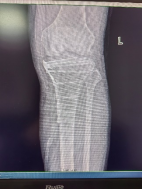

患者56歲男性,外傷致左踝部疼痛出血、腫脹畸形、活動受限,X線片顯示左脛腓骨遠端碎折,骨折斷端嵌插,骨折波及關(guān)節(jié)面,左脛骨近端內(nèi)側(cè)骨質(zhì)連續(xù)性中斷。

透視檢查骨折端